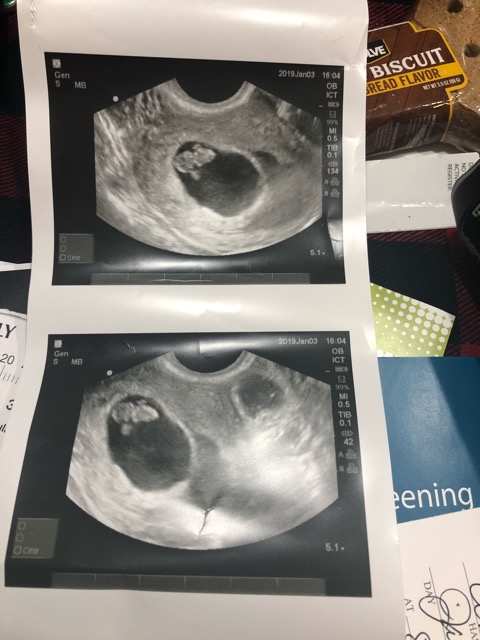

Any guess??

I’m 8 weeks and 1 day and baby is on my left side. Ramzi Theory’s Anyone💁🏼♀️